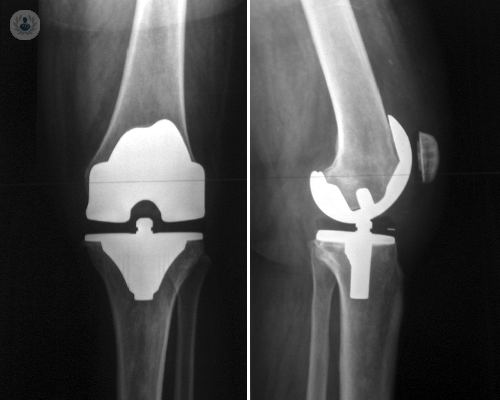

Reemplazo de cadera robótico de precisión submilimétrica: el nuevo estándar en recuperación y calidad de vida

La cirugía robótica permite una planificación personalizada y una ejecución con exactitud submilimétrica, mejorando la estabilidad, la seguridad y la recuperación funcional